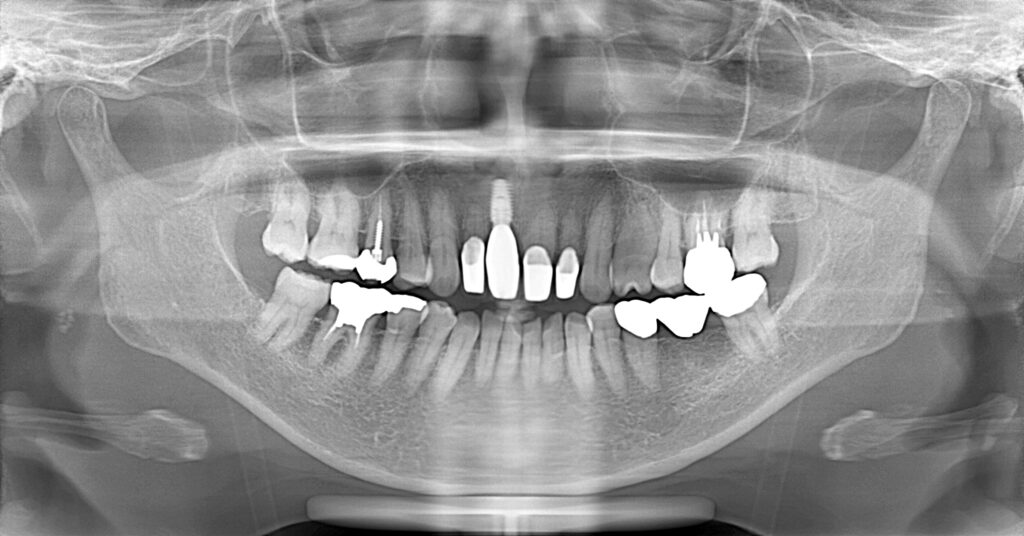

症例一覧 インプラント症例1 2024.11.25 治療内容インプラント主訴前歯部破折したためインプラント治療を行いたい費用¥671,000(1本)治療期間8ヶ月 インプラント症例2 前の記事 インビザライン症例2 次の記事